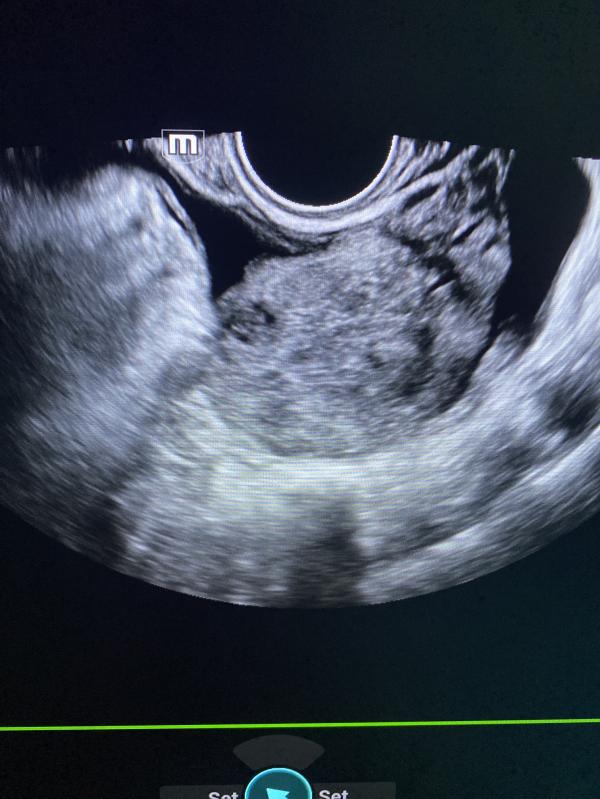

Узи миома матки: можно ли увидеть миому на снимке УЗИ? Случаи миомы и камней в почках

Можете на узи снимке увидеть миому матки?

Сегодня было много миом .